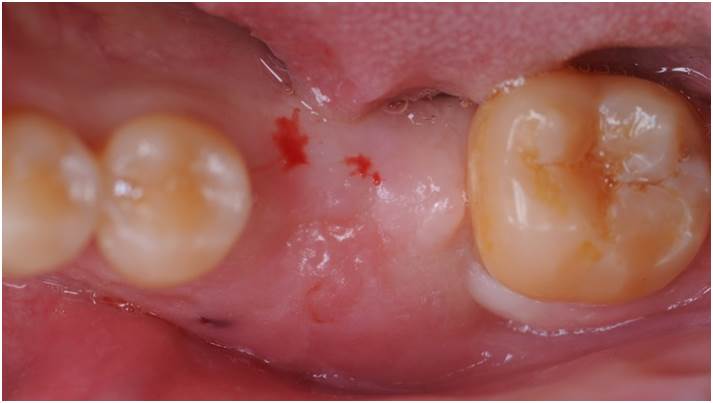

Clinical case: Single molar implant with bone augmentation

- Courtesy of Dr. Jung Sam Lee, Korea -

Keywords

AnyOne, bone augmentation, osteotomy socket, peri-implant tissue, autogenous bone, GBR, single replacement, Auto-Max, Dr. Jung Sam Lee

Products:

AnyOne implant system, Auto-Max